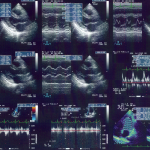

A transthoracic echocardiogram (TTE) is like a magical window into your heart’s inner workings, creating a captivating visual symphony of your heart’s movements. This noninvasive procedure is a go-to choice for gaining valuable insights into your heart’s health.

The Transesophageal Echocardiogram, often abbreviated as TEE, is a highly precise diagnostic procedure that utilizes echocardiography to capture detailed images of your heart and arteries. This advanced imaging technique is instrumental in evaluating cardiac function and assessing the overall performance of the heart.

The echocardiogram, a vital diagnostic tool embraced by physicians and cardiologists, unfolds as a masterpiece of medical imaging. This technique harnesses the power of sound waves to craft intricate images of the heart, providing invaluable insights into cardiac health.